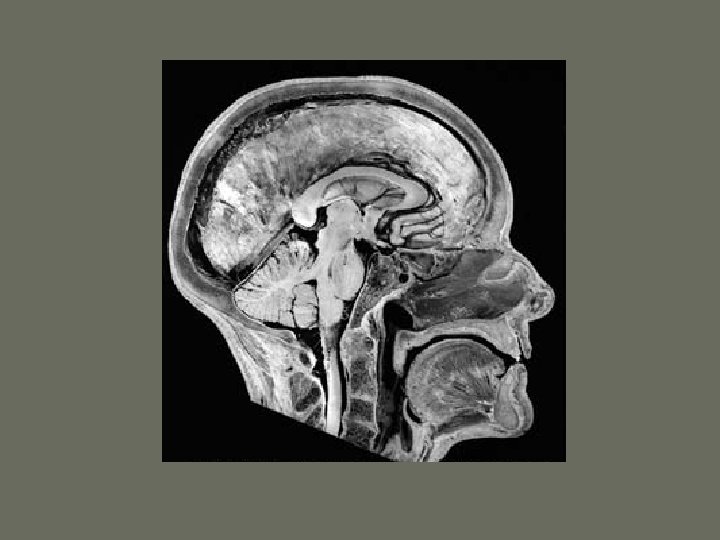

Parts of the Central Nervous System • • 2 hemispheres Brainstem Cerebellum Spinal cord

Each hemisphere has lobes: • • Frontal lobe Parietal lobe Temporal lobe Occipital lobe • Insular lobe • Limbic lobe

Ventricles and CSF

Ventricles and CSF • CSF is produced by the choroid plexus in the ventricles • The circulation is from the lateral ventricles to the third through the Monroe- aqueduct- IV ventricle- sub arachnoid space in skull and spineabsorption in sss and other sinuses through arachnoid granulations

Brain stem • Has 3 parts: midbrain, pons and medulla • Transports all the information to and from the brain • Centers for breathing and blood pressure • The origin or endpoint for cranial nerves • Contains the center of consciousness • Creates connections to the cerebellum